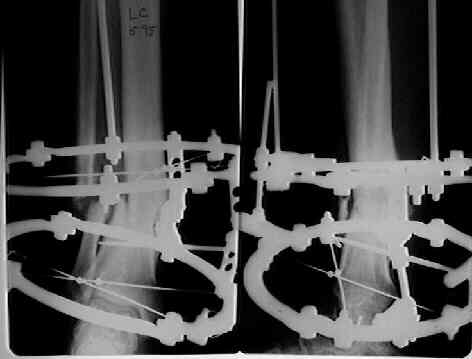

It seem a stiff pseudarthrosis. I will do a axial correction and lengthening if necessary with Ilizarov frame without any corticotomy. Probability of success will be 100% and relapse of infection 0%. You can see one case attached.